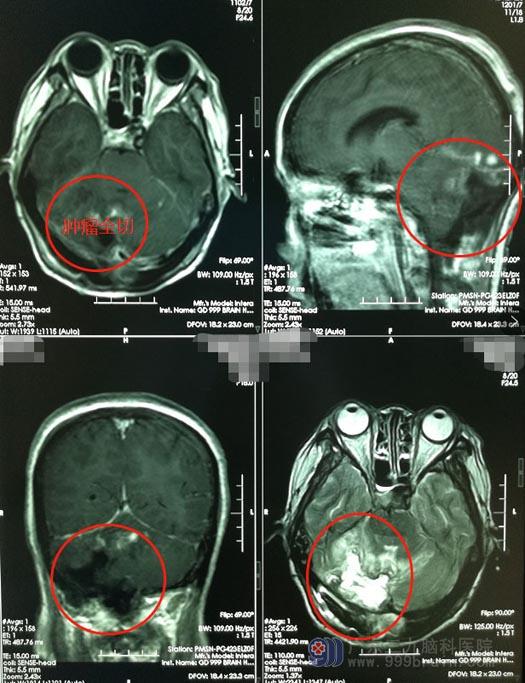

完善术前检查后,由鲁明主刀在全麻下行“右侧跨小脑幕上下巨大脑膜瘤切除术。手术很成功,重要的血管及神经均没有损伤。

术后,刘阿姨的情况一天比一天好转,精神也一天比一天好,各方面指标都检查正常,很快就可以出院了。